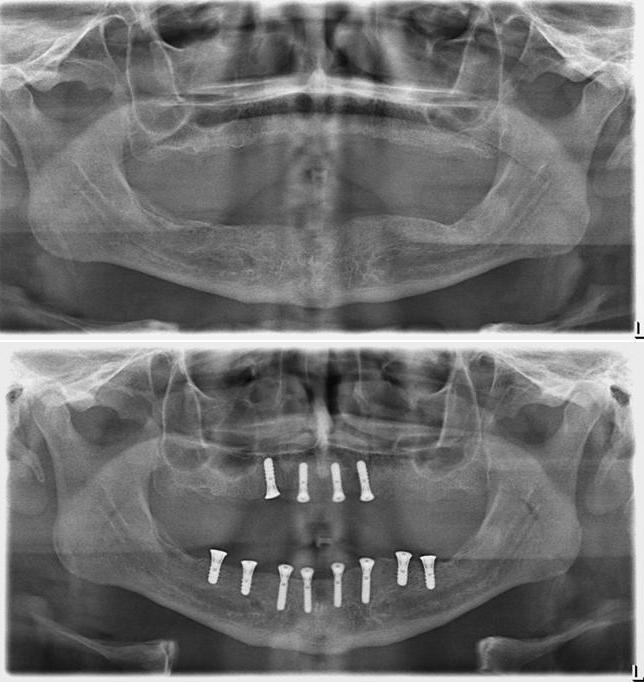

Dento-alveolar surgery (impacted teeth like wisdom teeth and canines, difficult tooth extractions, extractions on medically compromised patients, apicoectomy, bone grafting/bone harvesting or pre-prosthetic surgery) (See Images Below)

Surgery to insert osseo-integrated dental implants and Maxillofacial implants for attaching craniofacial prostheses (See Images Below)